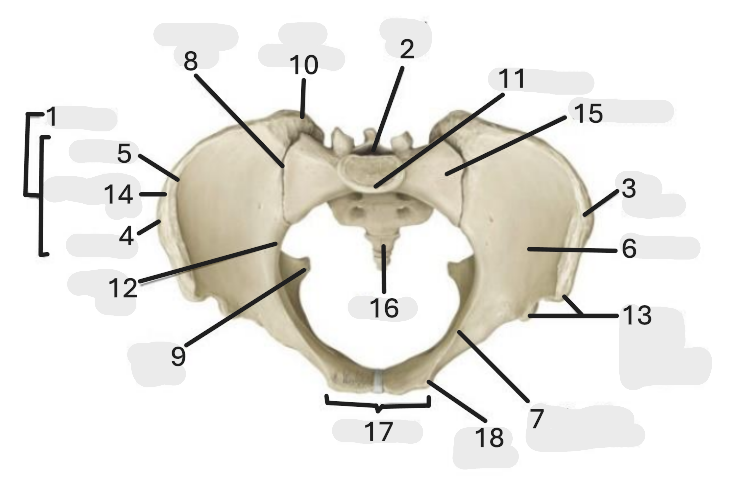

Where is the pelvic inlet

1

Where is the sacro-iliac joint

2

Where is the pubic tubercle

3

Where are the S1 body

4

Where is the ischial spine

5

Where is the ala of sacrum

6

Where is the anterior superior iliac spine

7

Where is the ischiopubic ramus

8

Where is the coccyx

9

Where is the obturator foramen

10

Where is the pubic symphysis

11

Where is the ischial tuberosity

12